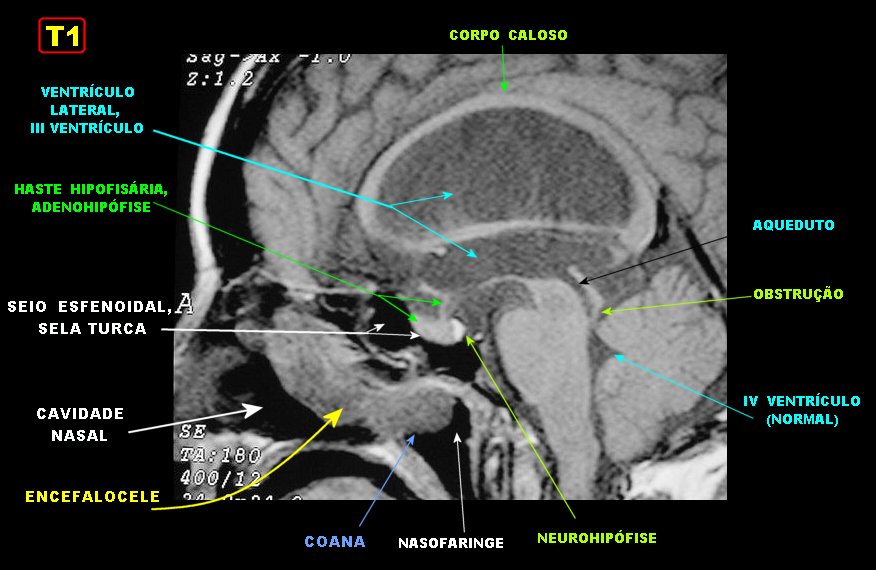

Фронтоэтмоидальное энцефалоцеле.

Цефалоцеле

Затылочное экцефалоцеле.